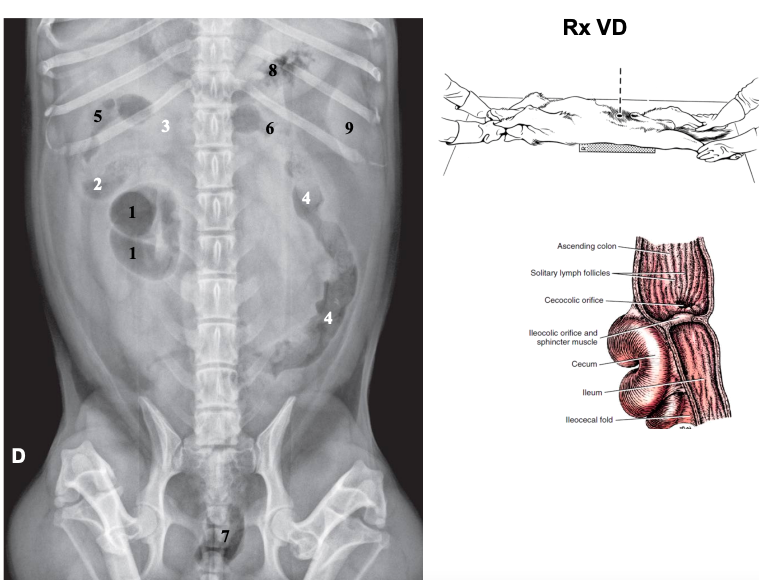

Radiografia ventrodorsal

La vertebra L2 tiene que caber entre 2,5 veces y 3,5 veces en el perro, entre 2,4 y 3 en el gato

Radiografia laterolateral

Dependiendo de la posición los gases van a un lado o a otro: Decúbito lateral derecho Radiografía Lateral

- Gas en fundus

- Se ve mejor cola del bazo

- Mayor separación de siluetas renales

Decúbito lateral izquierdo

- Gas en píloro

- Mejor visualización delduodeno